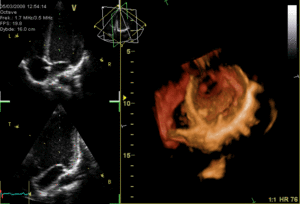

يتم تخطيط صدى القلب عبر المريء عن طريق مسبار يتم إدخاله عن طريق الفم إلى المريء، وذلك للحصول على "نافذة" أفضل موجات فوق صوتية|للموجات فوق الصوتية]] لرؤية الأقسام الخلفية من القلب، إذ أن هذه الجوانب تكون بعيدة عن الصدر، فتكون الصور التي يتم الحصول عليها من الصدر غير واضحة، بينما حينما يتم الفحص من المريء - الذي يُجاور القلب من الخلف مباشرة - أدق للأقسام الخلفية، كما يمكن إنتاج صور ثلاثية الأبعاد[5] لصمامات القلب.

يسمح التصوير عبر المريء بتحقيق تصوير بتمييز أعلى، وبخاصة للتفاصيل الدقيقة لحجرات القلب وصماماته، وذلك لأن المريء يقع مباشرة خلف القلب، بدون وجود الرئة كحاجز معيق بين مسبار الفحص وحجرات القلب، إذ أن الرئة بما تحتويه من هواء تعتبر معيقاً كبيراً لعمليات التصوير باستخدام الموجات فوق الصوتية. وتكون الدقة التصويرية أعلى من التصوير عبر الصدر[2] لأن المسبار يكاد يكون ملامساً للجدار الخلفي للقلب، ولايفصل بينهما إلا جدار المريء الدقيق نسبياً.

![]() صورة ثلاثية الأبعاد للصمام التاجي. |